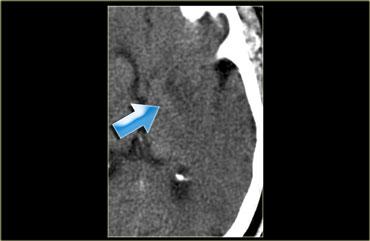

Các phát hiện trong trường hợp này rất tinh tế.

Có một vùng giảm tỷ trọng nhẹ ở vỏ não đảo bên phải, đây là vùng chúng ta luôn xem xét đầu tiên.

Trong trường hợp này, hình ảnh gợi ý nhồi máu não, nhưng đôi khi ở bệnh nhân cao tuổi có bệnh lý chất trắng (leukoencephalopathy) thì rất khó phân biệt.

CTA đã được thực hiện (xem hình tiếp theo).

Bây giờ chúng ta có thể tự tin với chẩn đoán nhồi máu MCA.